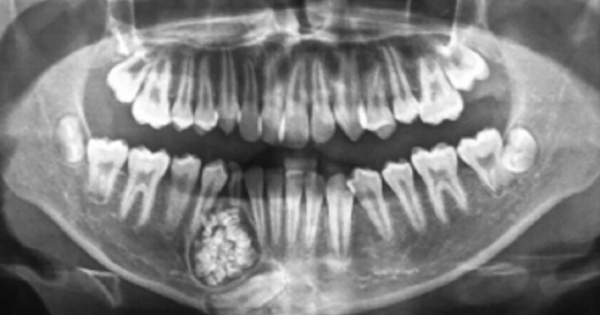

Lấy gần 100 chiếc răng trong khối u răng của bé trai 13 tuổi

Bé trai 13 tuổi được gia đình đưa đến bệnh viện khám vì răng mọc lệch và chậm thay răng. Thế nhưng, các bác sĩ phát hiện một khối u răng ở xương hàm dưới bệnh nhân, bên trong khối u chứa gần 100 chiếc răng nhỏ.